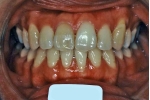

治療前後の比較

|